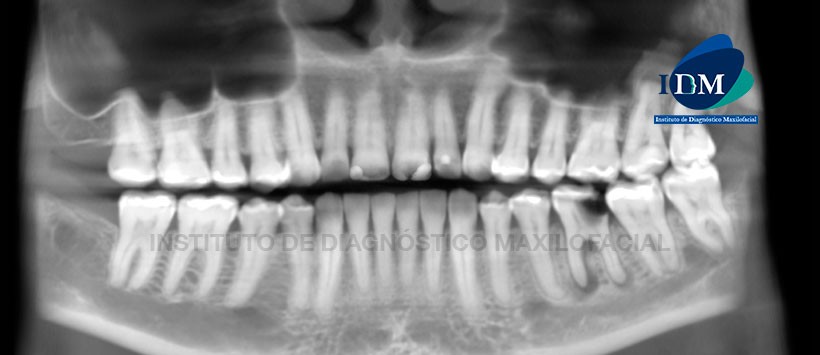

En la reformación panorámica de la tomografía volumétrica (CBCT) (Figura 1), se aprecia proceso osteolítico periapical de raíz mesial y distal de la pieza 3.6 con aumento de la densidad ósea circundante compatible con osteítis condensante; así mismo se aprecia múltiples restauraciones, pieza 2.7 con lesión de caries recidivante con compromiso pulpar y proceso osteolítico periapical adyacente al seno maxilar.